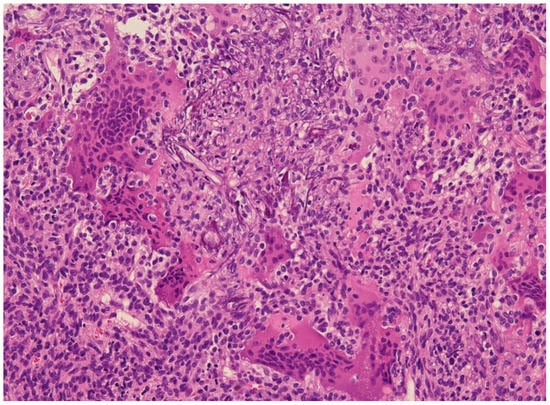

5. Histology

- Folpe, A.L.; Fanburg-Smith, J.C.; Billings, S.D.; Bisceglia, M.; Bertoni, F.; Cho, J.Y.B.; Econs, M.J.; Inwards, C.Y.; de Beur, S.M.J.; Mentzel, T.; et al. Most Osteomalacia-associated Mesenchymal Tumors Are a Single Histopathologic Entity: An analysis of 32 cases and a comprehensive review of the literature. Am. J. Surg. Pathol. 2004, 28, 1–30. [Google Scholar] [CrossRef]

- Weidner, N.; Santa Cruz, D. Phosphaturic mesenchymal tumors. A polymorphous group causing osteomalacia or rickets. Cancer 1987, 59, 1442–1454. [Google Scholar] [CrossRef]

- Agaimy, A.; Michal, M.; Chiosea, S.; Petersson, F.; Hadravsky, L.; Kristiansen, G.; Horch, R.E.; Schmolders, J.; Hartmann, A.; Haller, F. Phosphaturic Mesenchymal Tumors: Clinicopathologic, Immunohistochemical and Molecular Analysis of 22 Cases Expanding their Morphologic and Immunophenotypic Spectrum. Am. J. Surg. Pathol. 2017, 41, 1371–1380. [Google Scholar] [CrossRef]